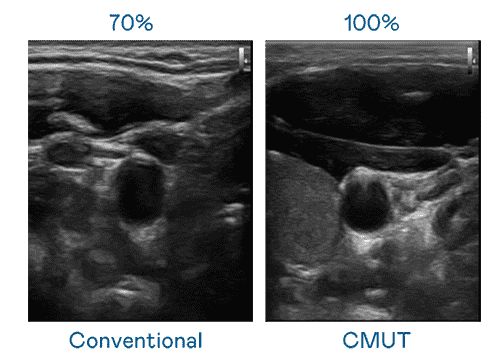

CMUT 技术是一种用电容式微机电元件来产生超音波讯号的技术。。。。与传统 PZT 压电式技术相比,,,CMUT 频宽增加 30%,,,,更宽频的超音波讯号让影像解析度大幅提升,,,,是实现高影像品质医疗超音波扫描、、促进精准医疗发展的关键技术。。。。

大频宽带来超清晰影像

超音波影像的解析度高低,,,,首先取决于探头能发出的讯号频宽。。。壹号平台 CMUT 可提供高清晰的超音波讯号,,,,提供高频宽、、高灵敏度、、、影像纹理细节更高的超音波影像,,,,协助医护人员缩短影像判读时间及利用精准的医疗影像进行诊断。。